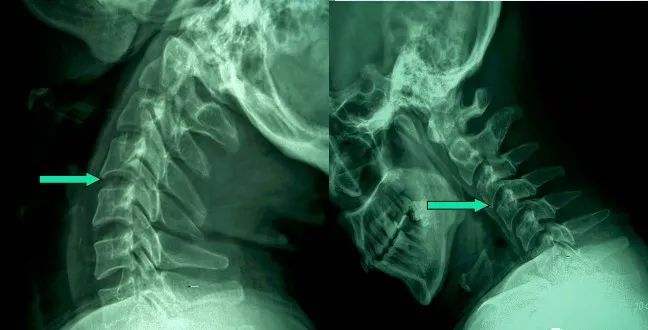

5、頸椎骨折

由于頸椎骨折,可造成出血,水腫,或碎骨片移位波及到椎間孔或椎管,直接壓迫頸神經根或頸脊髓。骨癡的形成,使椎管、椎間孔發生狹窄性改變,產生脊髓、神經根的受壓癥狀。